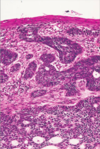

Describe the typical presentation of plaque psoriasis.

- This is a psoriasiform reaction pattern

- Tends to present as silvery plaques on the extensor surfaces

How is the keratinocyte turnover time different in psoriasis compared to normal skin?

- Normal skin turnover = 50 days (time for keratinocyte to go from the bottom of the epidermis to the top)

- Psoriasis = 7 days

- This leads to thickening of the epidermis and you get a layer of parakeratosis at the top

Which layer of the epidermis disappears in plaque psoriasis and why?

Statum granulosum - there is not enough time to form it

What can neutrophil recruitment to the epidermis in plaque psoriasis cause?

Formation of Munro’s microabscesses